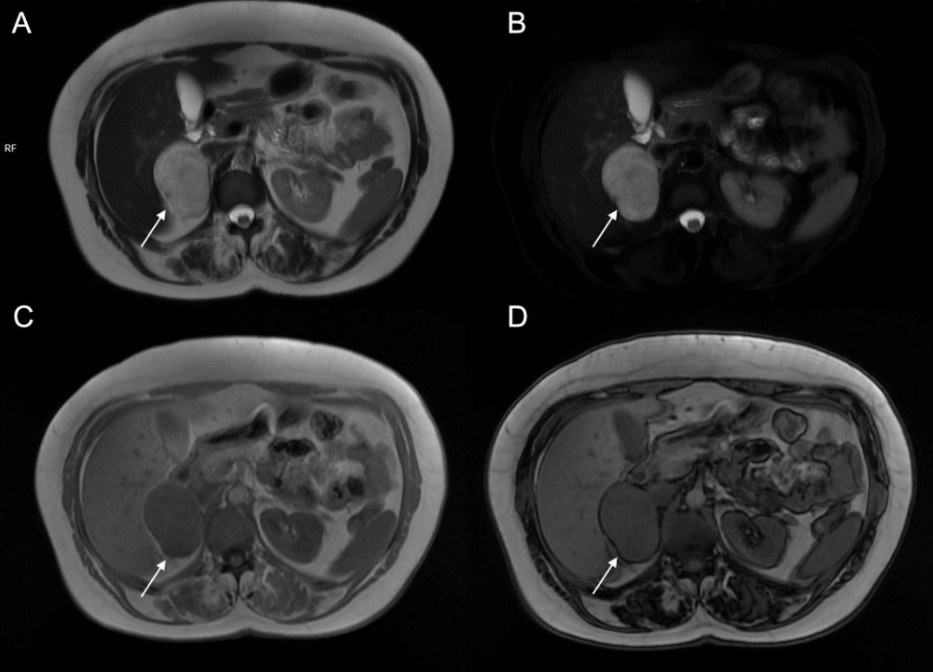

This is a common, harmless lump that usually doesn’t cause symptoms. On MRI, they show a characteristic loss of signal on special out-of-phase sequences because the fat cancels out the signal from water20. This helps distinguish them from other tumours. They usually appear small, smooth, and uniform.

Signal Drop on Out-of-Phase Imaging: This is a technical phrase used by radiologists. It means that, when certain MRI pictures are taken (so-called “out-of-phase” images), the spot becomes less visible or darker, which is a classic sign of a fat-rich (lipid-rich) adenoma, and usually points toward a benign lump17.